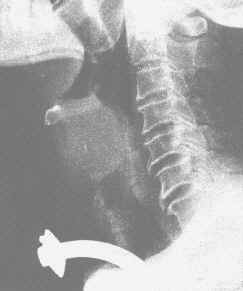

(1)X線檢查:X線喉側位片及喉頭正位體層片可以明確病變的大體部位、大小、形狀及軟骨、氣管或頸椎前軟組織變化情況。必要時,可行喉造影。

喉癌(平片)(1) 心理護理:做好病人及家屬的安慰、解釋工作,關心、體貼病人,滿足其合理需求,使病人以良好的心理狀態迎接手術。